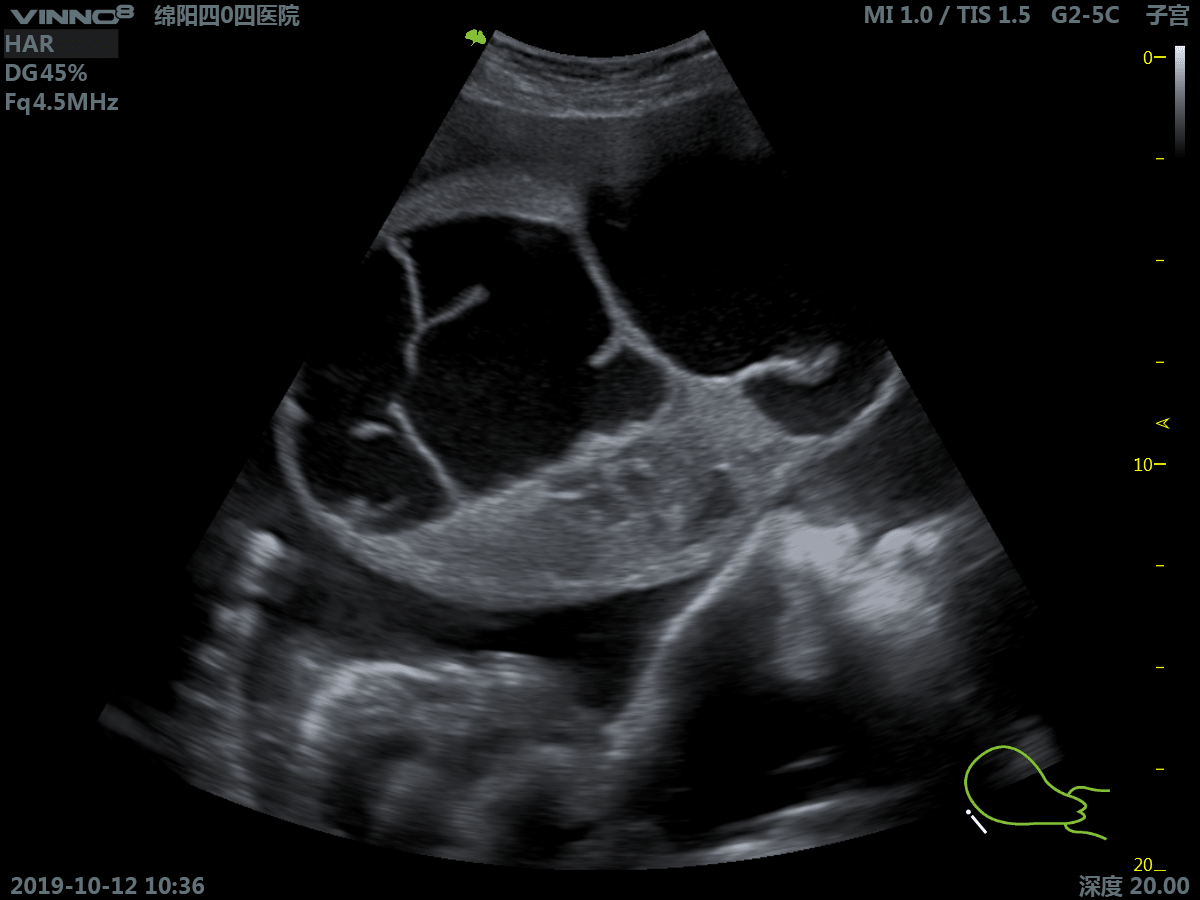

Клиническое применение:

- брюшная полость

- акушерство/внутриутробное развитие

- гинекология

- трансвагинальное обследование

17. 3D. Режим получения трехмерного акустического изображения.

18. Real time 3D(4D) – B (HARMONIC) Режим трёхмерного (четырехмерного, четвертая ось - время) сканирования в реальном времени совместно с режимом тканевой гармоники.